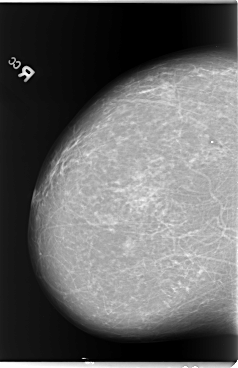

B_3105_1.LEFT_MLO

LEFT_CC LINES 5888 PIXELS_PER_LINE 3656 BITS_PER_PIXEL 12 RESOLUTION 50 OVERLAY

FILE: B_3105_1.LEFT_CC.OVERLAY

TOTAL_ABNORMALITIES 1

ABNORMALITY 1

LESION_TYPE CALCIFICATION TYPE PLEOMORPHIC DISTRIBUTION CLUSTERED

LESION_TYPE MASS SHAPE IRREGULAR MARGINS ILL_DEFINED

ASSESSMENT 4

SUBTLETY 3

PATHOLOGY BENIGN

TOTAL_OUTLINES 1

BOUNDARY